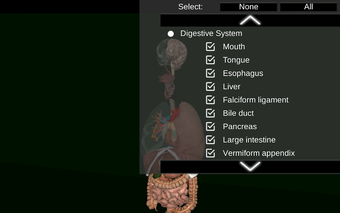

此应用程序显示人体器官的三维模型和所有器官的描述。

您可以触摸每个器官,如心脏、大脑、肺、生殖系统、肝脏、肠道、卵巢、睾丸、胃、肾脏等。

该应用程序旨在补充医学、生物学或其他领域的解剖学研究。

您可以使用该应用程序找出哪些是不同的身体器官以及它们的功能。